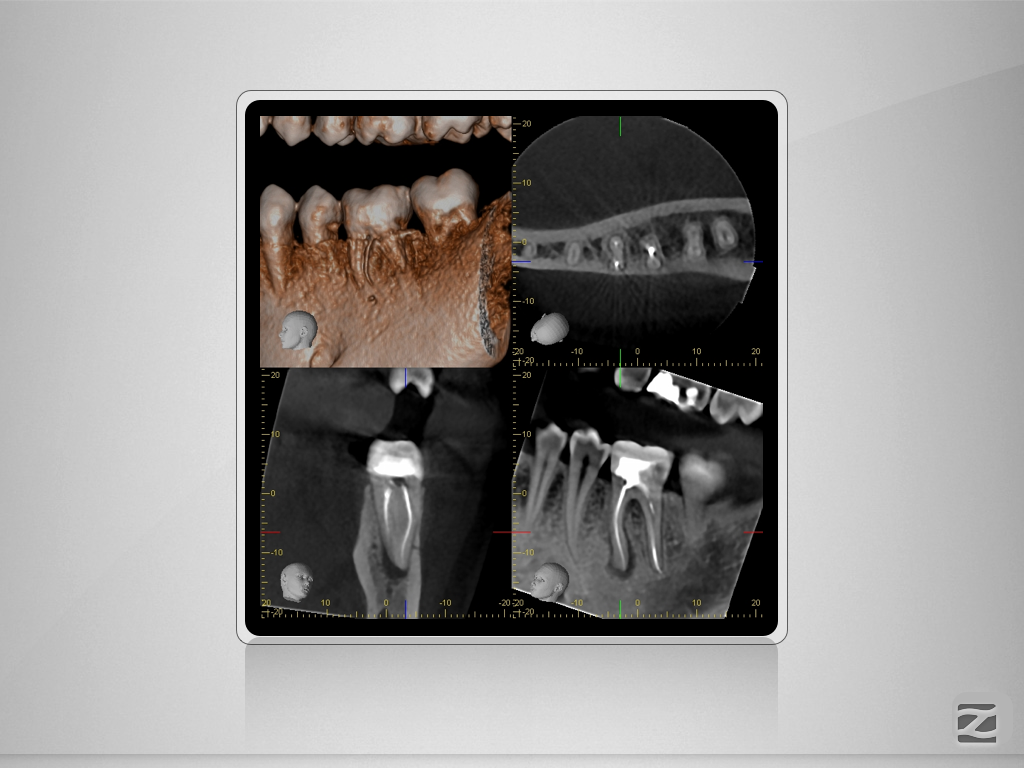

36D.006

Fraktur auf voller Arbeitslänge